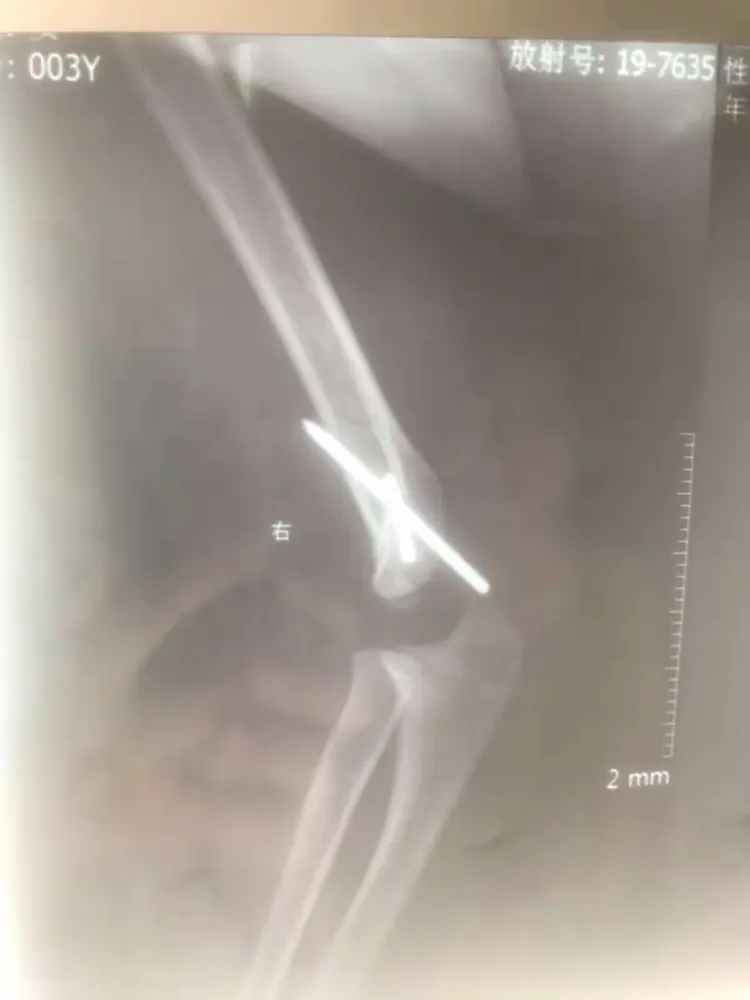

肱骨外髁骨折程度[s0]肱骨外髁骨折分型[s1]肱骨外髁骨折的临床表现[s2]肱骨外髁骨折Ⅲ型复位手法[s3]肱骨外髁骨折,保守治疗可以吗[s4]小儿肱骨外髁骨折[s5]儿童肱骨外髁骨折,医生不说你很可能永远都不会知道的[s6]不同类型的肱骨外髁骨折[s7]肱骨外髁骨折概述[s8]六、肱骨外髁骨折 - 图1[s9]六、肱骨外髁骨折 - 图2[s10]图片[s11]肱骨外髁骨折 m.haodf.com[s12]图片[s13]肱骨外髁骨折[s14]img[s15]肱骨外髁骨折.[s16]分期矫正儿童肱骨外髁骨折不愈合伴肘外翻畸形[s17]肱骨外髁骨折[s18]肱骨外髁骨折翻转90°,复位后克氏针或螺钉固定(自ao)[s19]右肱骨外髁骨折切开复位内固定术[s20]img[s21]img[s22]赵景新's media[s23]一例儿童右肱骨外髁骨折病例[s24]肱骨外髁骨折,保守治疗可以吗[s25]小儿肱骨外髁骨折[s26]肱骨外髁骨折固定[s27]肱骨外髁骨折 www.iiyi.com[s28]小儿肱骨外髁骨折的诊断和治疗[s29]右肱骨内外髁骨折[s30]图36-48 肱骨外髁骨折的不同程度移位 a型无移位;b型中度移位;c型完全移位伴旋转[s31]肱骨外髁骨折 www.haodf.com[s32]肱骨外髁骨折 www.haodf.com[s33]问:左肱骨外髁骨折,左肘关节脱位,6.[s34]儿童肱骨外髁骨折 - 小红书[s35]儿童肘关节损伤之--肱骨外髁骨折[s36]▲右侧肱骨外髁骨折闭合复位克氏针固定及石膏固定术后。“幸亏在掉落的[s37]肱骨外髁骨折 www.guahao.com[s38]肱骨头及外髁骨折,求诊治方案,手术还是非手术[s39]